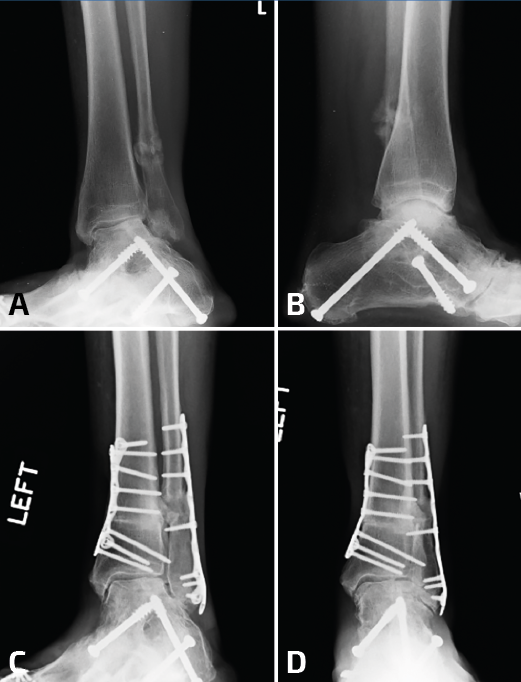

Figura 4. Cuando se realiza la elongación del peroné, este se mueve hacia proximal, evitando la elongación distal. Para evitar esto, se colocan 2 pines proximales a la osteotomía (A). Tras el desbridamiento de la sindesmosis, se elonga el peroné (B) y para mantener la elongación se colocan 2 pines distales a la osteotomía (C) y luego se colocan el injerto y la placa (D).

Una vez más, se desbrida el tejido fibrótico de la cara interna del peroné, pero se deja intacto el ligamento talofibular anterior y el ligamento calcáneo fibular. Para este tipo de osteotomías transversas es importante comprender que, en el proceso de elongación del peroné, al insertar el separador laminar o utilizar el distractor de agujas, se empujará simultáneamente el peroné hacia proximal(10). Por lo tanto, resulta útil insertar 1 o 2 agujas de 1,6 mm en el peroné en la zona proximal a la osteotomía pasando por la tibia para evitar el movimiento del peroné hacia proximal y que solamente se produzca la elongación distal (Figura 4). Una reconstrucción exitosa requiere el posicionamiento anatómico del maléolo externo en la escotadura peronea de la tibia que solo puede detectarse con visualización directa.

La distracción estable es importante durante el procedimiento de elongación del peroné, dado que permite una colocación más sencilla del material de osteosíntesis. Se han descrito varios métodos para poder fijar el astrágalo a la cara interna de la tibia: se pueden utilizar clavos Steinmann desde el peroné distal hasta el astrágalo, o bien se puede insertar una aguja para fijar al astrágalo contra la cara interna de la tibia, cerrando así el espacio de la gotera medial. Otra alternativa sería la utilización de una pinza de reducción de puntas que se coloca en el extremo distal del maléolo externo y el extremo distal del maléolo interno para restablecer el ángulo intermaleolar. Tras una correcta elongación y rotación, se restablece el espacio claro medial, el paralelismo entre las superficies articulares de la tibia y el astrágalo en la mortaja, y una correcta relación entre ambos maléolos (Figura 5).

Figura 5. En este caso, se observa ensanchamiento de la sindesmosis más consolidaciones viciosas del peroné y el maléolo medial (A). Se debe comenzar por la gotera medial para limpiar todo el tejido cicatrizal remanente. La incisión fue más larga de lo habitual, ya que se planificó una osteotomía del maléolo medial. Tras la reducción y la elongación del peroné, se coloca una pinza de reducción en el eje axial entre la tibia y el peroné (C, D). Al continuar con inestabilidad posterior a la colocación de 2 tornillos (E), se decidió realizar una artrodesis de la sindesmosis